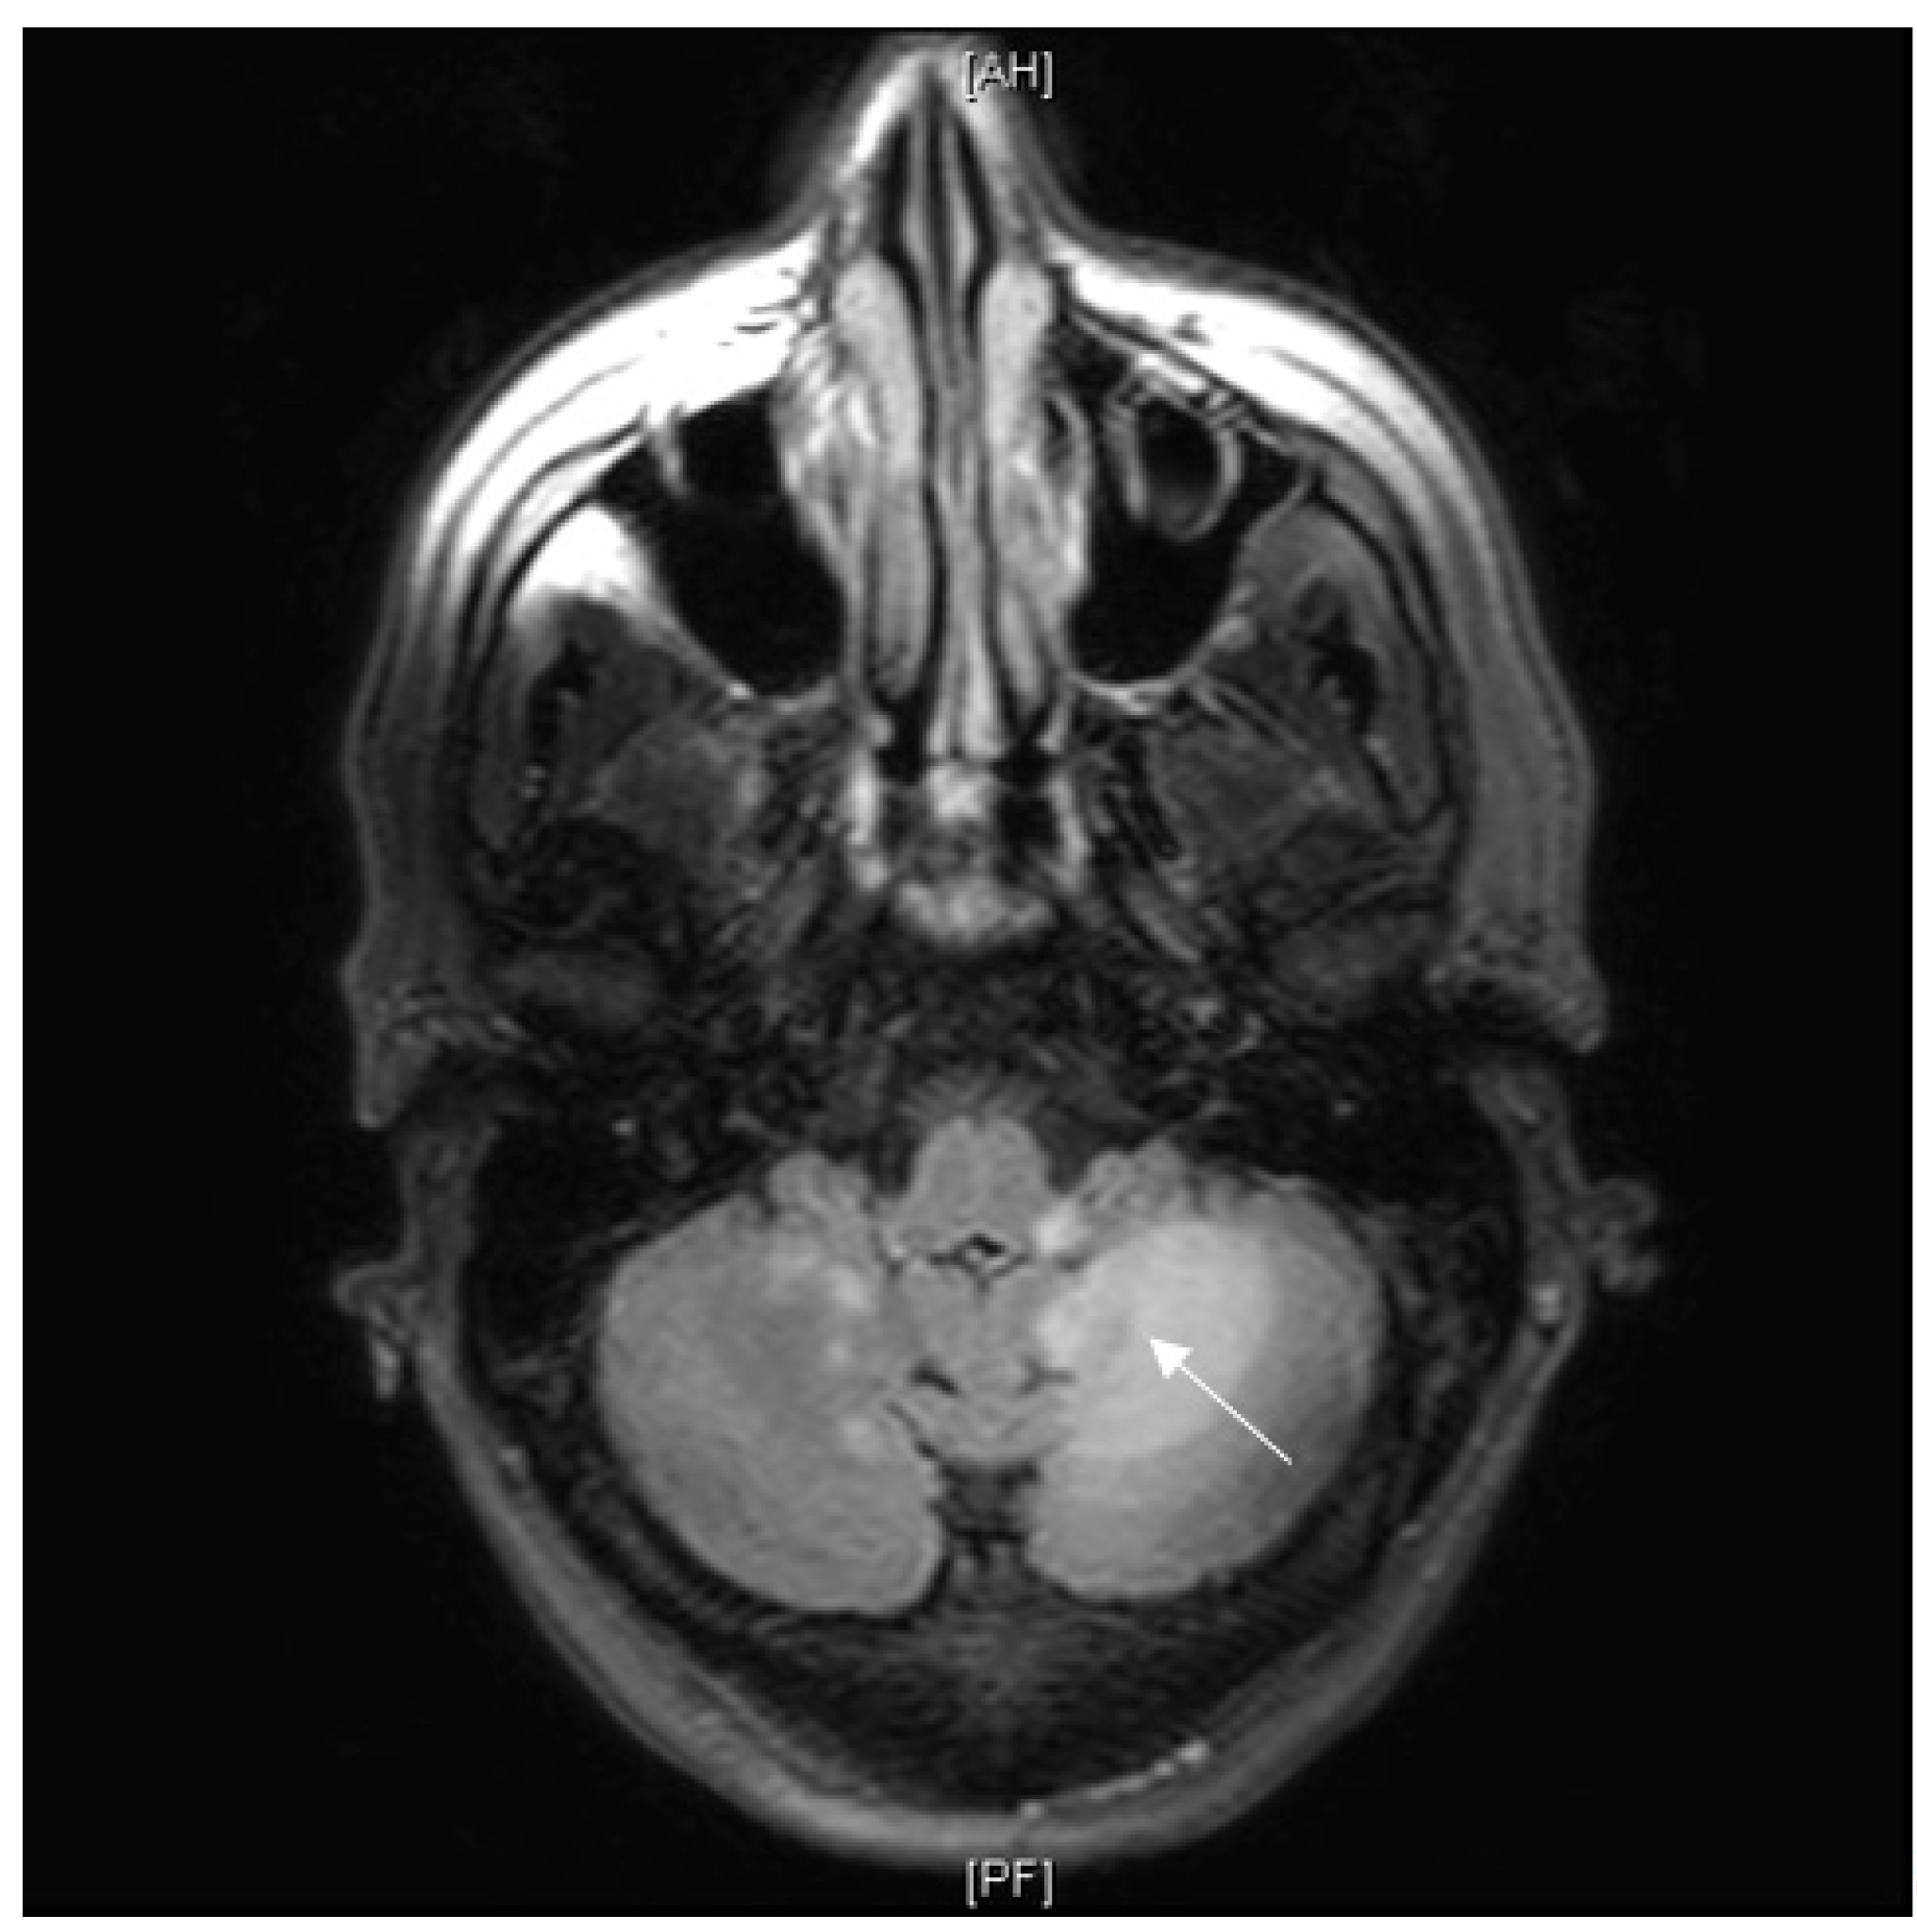

3.7. Neurosarcoidosis

3.7.1. Case Description

3.7.2. Discussion